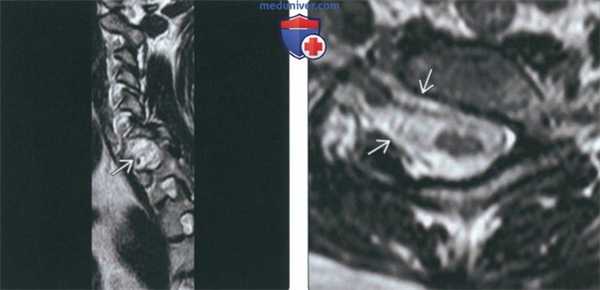

(Слева) Т2-ВИ, сагиттальная проекция: тяжелая остроугольная кифотическая деформация верхне-грудного отдела позвоночника.

На вершине деформации определяется в значительной степени гипопластичный передний полу-позвонок, а также нетипичен вид остальных позвонков, свидетельствующий о множественных аномалиях формирования и сегментации позвонков.

(Справа) Т1-ВИ, аксиальная проекция (тяжелый кифосколиоз): нормальный спинной мозг на фоне сужения окружающего участка спинномозгового канала связанного с множественными врожденными аномалиями формирования позвонков.